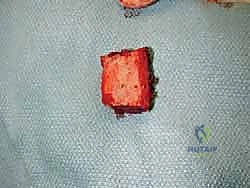

الخطوة الثالثة: إزالة المفصل القديم (Explant Removal)

يتم استخراج المكونات المعدنية والبلاستيكية لمفصل (Agility) القديم بحرص بالغ للحفاظ على ما تبقى من العظم السليم.

الخطوة الرابعة: تنظيف العظم والترقيع (Debridement and Bone Grafting)

يتم تنظيف الأنسجة الملتهبة والأكياس العظمية. ونظراً لأن مفصل (Agility) يترك فراغاً كبيراً بعد إزالته، يتم استخدام طعوم عظمية (Autograft من حوض المريض أو Allograft من بنك العظام) لملء الفراغات وبناء أساس قوي.